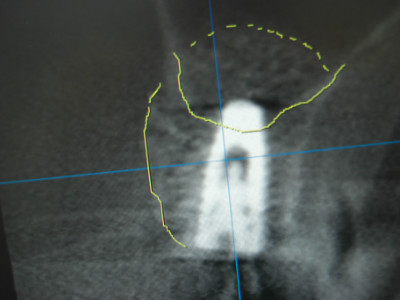

この患者様は右上4番頬側が腫れて痛くて噛み込めないとのことで来院されました。CTにて精査させて頂きましたところ、4番が歯根破折を起こし保存不可能な状態でしたね。

抜歯と同時に埋入できればと考えていたのですが上顎洞底までの骨の厚みが7ミリ程でしたので、抜歯と同時にソケットリフトを施術し洞底を拳上し側方にGBR(骨造成)して予知性のあるインプラント埋入オペとすることにいたしました。